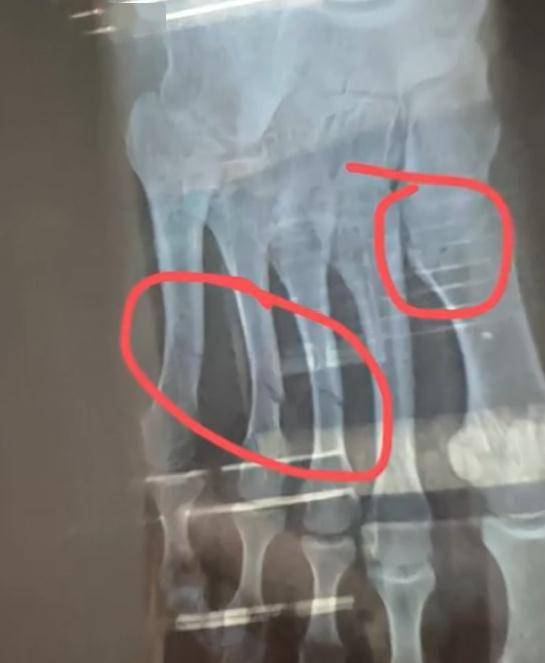

健身房工作人员梁教练称,当时视频中的白衣男生正在单侧卸片,致使健身器械失衡侧翻,砸中一旁的女生。女孩被砸中了脖子胸和腰部等位置,随后被送去就医。在经过CT等全身检查后,发现她脚趾断了4根。